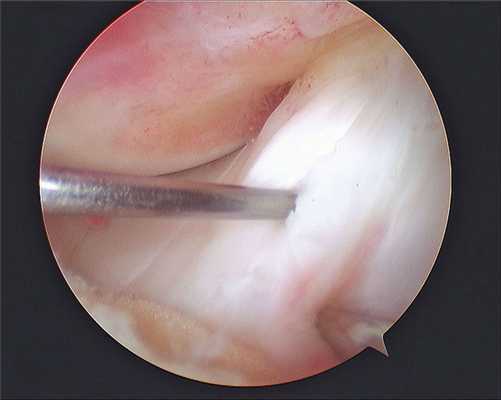

Артроскопия коленного сустава при повреждении менисков: описание методов и техник

Все артроскопические вмешательства выполняют под визуальным контролем. Для визуализации внутрисуставных структур в суставную полость вводят артроскоп, который представляет собой жестко соединенные между собой трубку и окулярный оголовок. Изображение из артроскопа выводится на экран в операционной, что позволяет хирургу контролировать свои действия, а пациенту — наблюдать за ходом хирургического вмешательства.

Сначала ногу пациента сгибают и через небольшой разрез вводят канюлю. Затем — разгибают и через канюлю вводят артроскоп. Инструменты для артроскопических манипуляций вводят через небольшие разрезы длиной 4-5 мм. После операции артроскоп и все инструменты извлекают, а послеоперационные раны зашивают и заклеивают лейкопластырем.